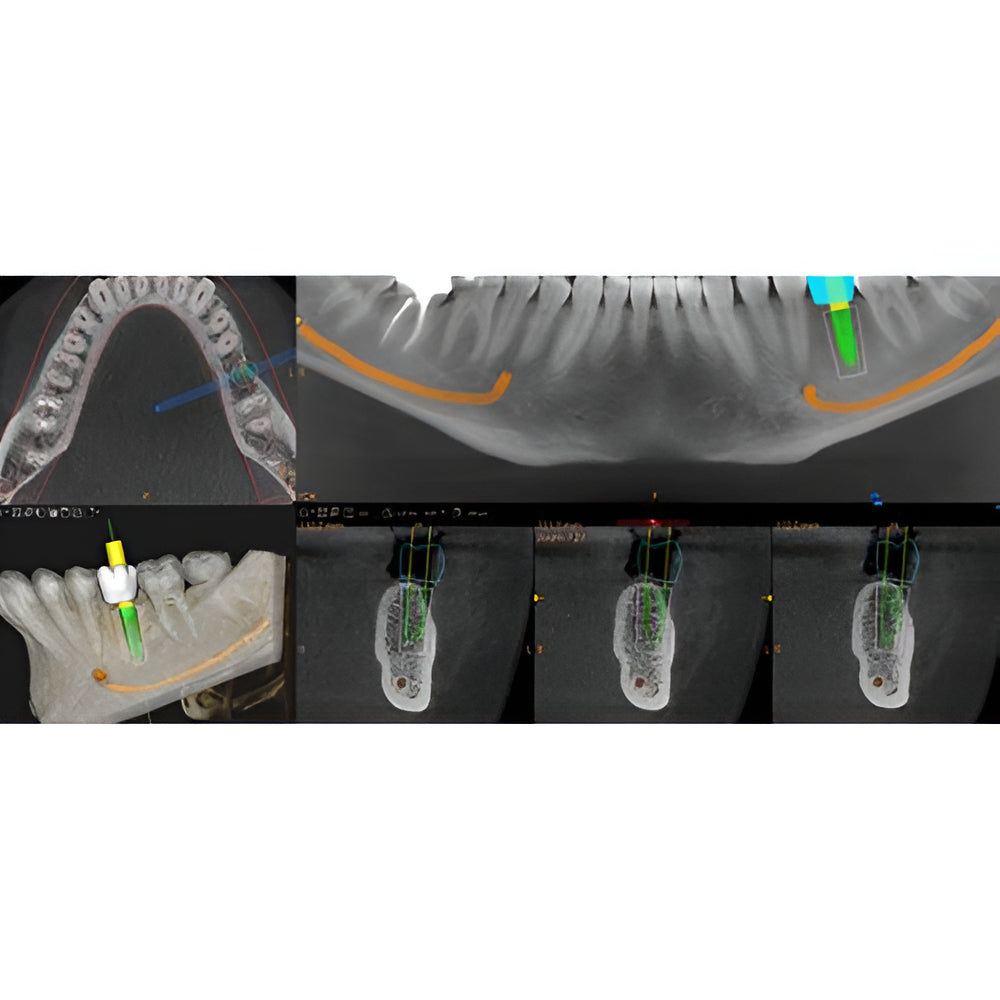

Enter a world of crystal-clear 3D images with the CS 8200 3D Access-a CBCT system that’s state-of-the-art, but intuitive and easy to use, taking your dental practice to the next level. Enjoy CBCT imaging that’s easier than you think and built on an open platform so that you can activate your future practice here and now.

- Field Of View: 4x4, 5x5, 8x5, 8x9, 12x5, 12x10

- Versatile 4-in-1 solution ideal to expand treatment options